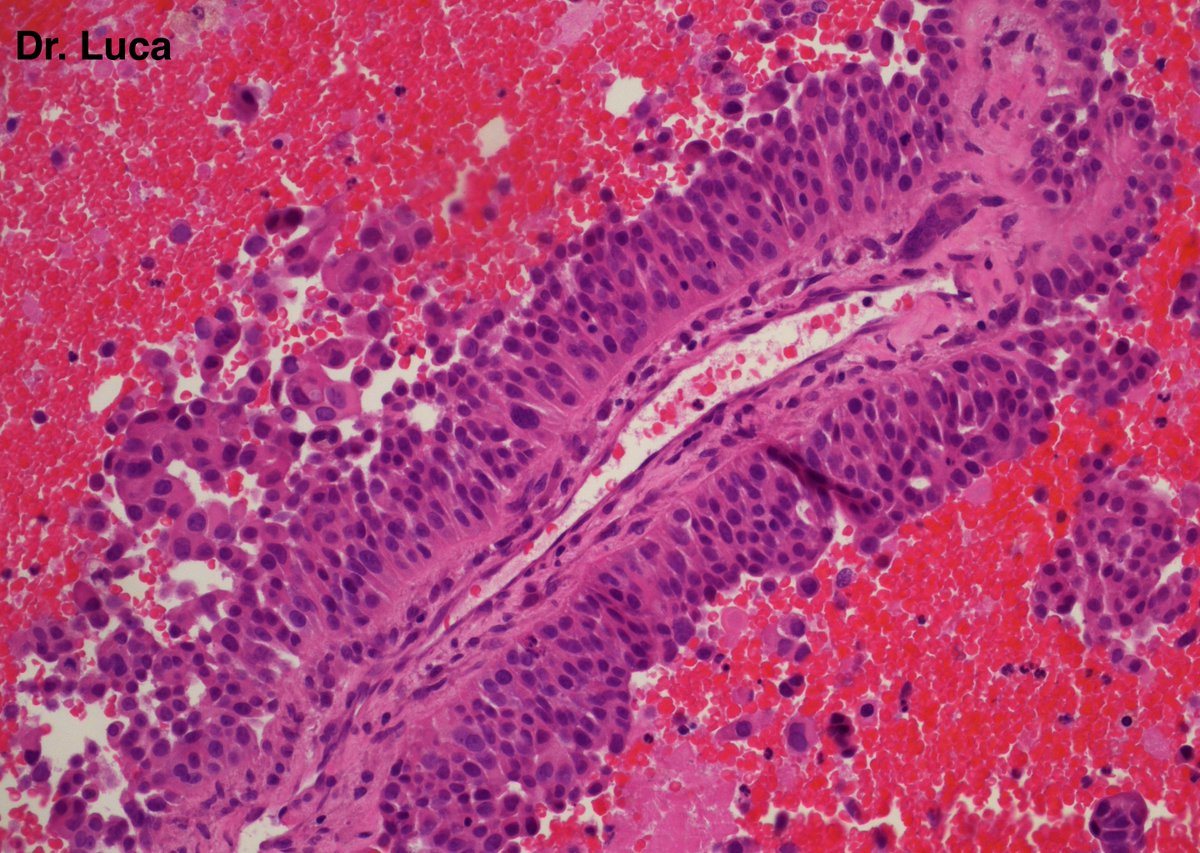

71yoM, bone metastasis, what's your quick H&E diagnosis? (no IHC) @AkgulMd @JPintoPath @slusagar @EKoubaMD @Pathmath1 @s_prendeville @goziemnweke @SumantaDas_7 @D4L14H @PoloniaAntonio @kriyer68 @md_kyle @kis_lorand @MarcosLepeMD @ivanaspath @pathobot #Pathology #PathTwitter

22

25

63